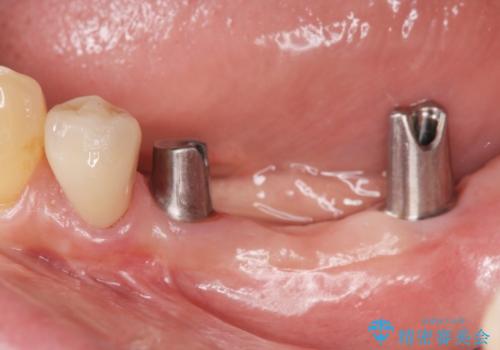

チタンカスタムアバットメントを用いた清掃性の高いインプラント治療

清掃のしやすさと審美性・強度に優れるチタン製カスタムアバットメントとジルコニアクラウンによる補綴治療を計画します。

- 113.3万円(インプラント×2・仮歯×3・チタンカスタムアバットメント×2・ジルコニアクラウン×3)費用は治療当時の料金となります